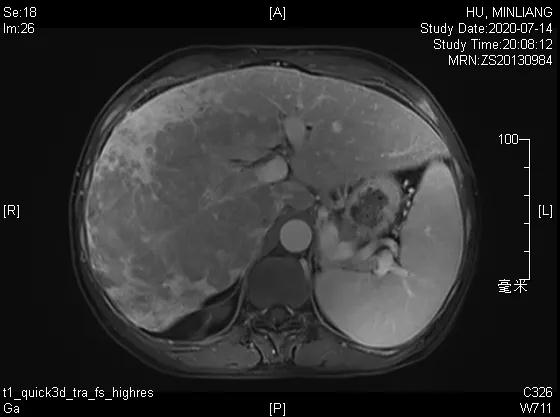

术前影像学检查:

肝脏弹性超声:12kPa。腹部MRI平扫+增强:肝巨块结节性HCC(最大径18.4cm)伴肝内多发转移(最大径3.5cm),肝右静脉广泛癌栓形成;肝硬化伴门脉高压、脾大、少量腹水;肝囊肿;双肺多发转移。胸部CT平扫:两肺多发转移,两肺气肿伴肺大泡,两肺散在慢性炎症,右侧少量胸水。

Δ肝脏MRI,最大肿瘤18.4cm